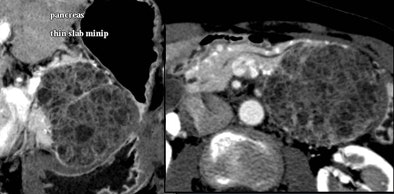

Small cystic lesions not worrisome for malignancy under 3 cm include side branch IPMNs, and serous microcystic adenomas, which are easily characterized by their honeycomb matrix that is also easily seen on ultrasound, Jeffrey said.

Serous cystic tumors are by far the most common pancreatic cystic lesions, Jeffrey said. They are nearly always microcystic, with macrocystic serous lesions occurring in about 4% of cases. They also are benign and can be managed with follow-up but not surgery, he said.